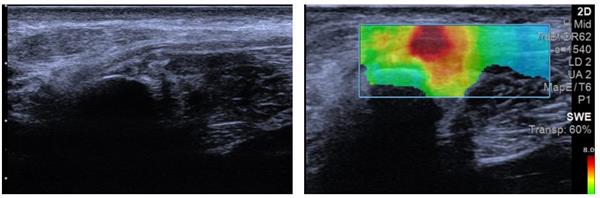

为进一步明确病情,团队为小彭开展了超声造影联合评估。首先通过弹性成像检测,初步判断神经组织硬度变化,图像中红色区域提示局部组织硬度增高,与腓总神经卡压部位高度相关。高频超声检查也清晰发现,受压的腓总神经局部增粗、回声变低,卡压点近端形成了梭形的膨大。

患者腓总神经超声扫查图;患者弹性检测区域图

声像图示:左侧腓总神经腓骨颈(FI)处变细,近端增粗,神经回声减低,神经外膜回声增强,神经束膜显示不清